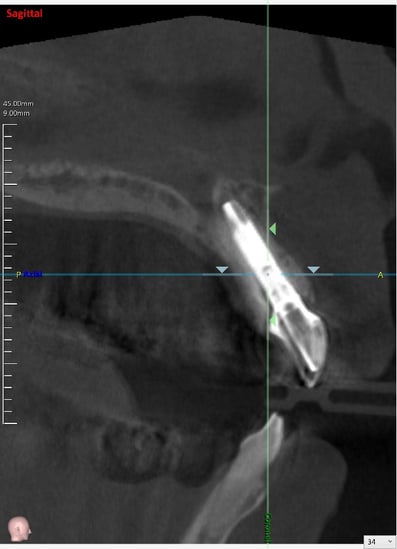

抜歯した直後にインプラントを埋入し、仮の歯を作製、唇側の骨のボリュームを保つために人工骨と結合組織を同時に移植する非常に優れた方法です。

既存の骨の形態分類(ClassⅠ〜Ⅳ)のClassⅢまでは埋入可能とされています。